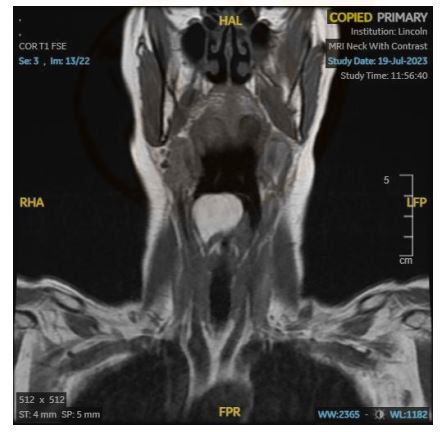

Transnasal flexible laryngoscopy revealed a large, round, and smooth mass situated over the right supraglottic area, covered by healthy mucosa. The origin of the mass could not be identified, and visualization of the vocal cords in their entirety was impeded due to the mass. A subsequent magnetic resonance imaging (MRI) scan of the neck with contrast delineated a well-defined, non-enhancing, fat-containing lesion in the right supraglottic region and was reported as measuring 2.9 cm in its widest dimension (see Figures 1B & 1C).